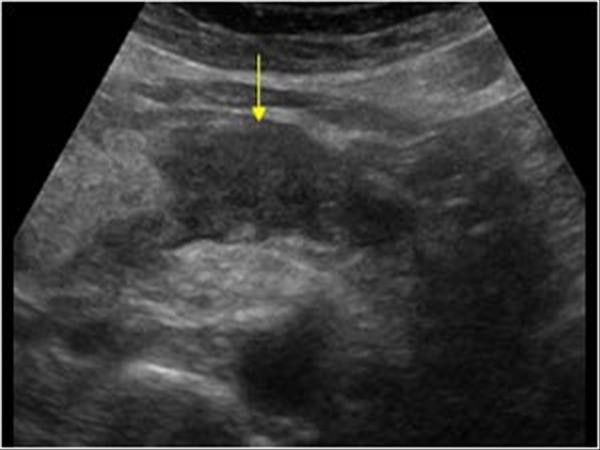

U tụy

» Thông tin: Nữ giới – 57 tuổi.

» Lâm sàng: Sút cân.